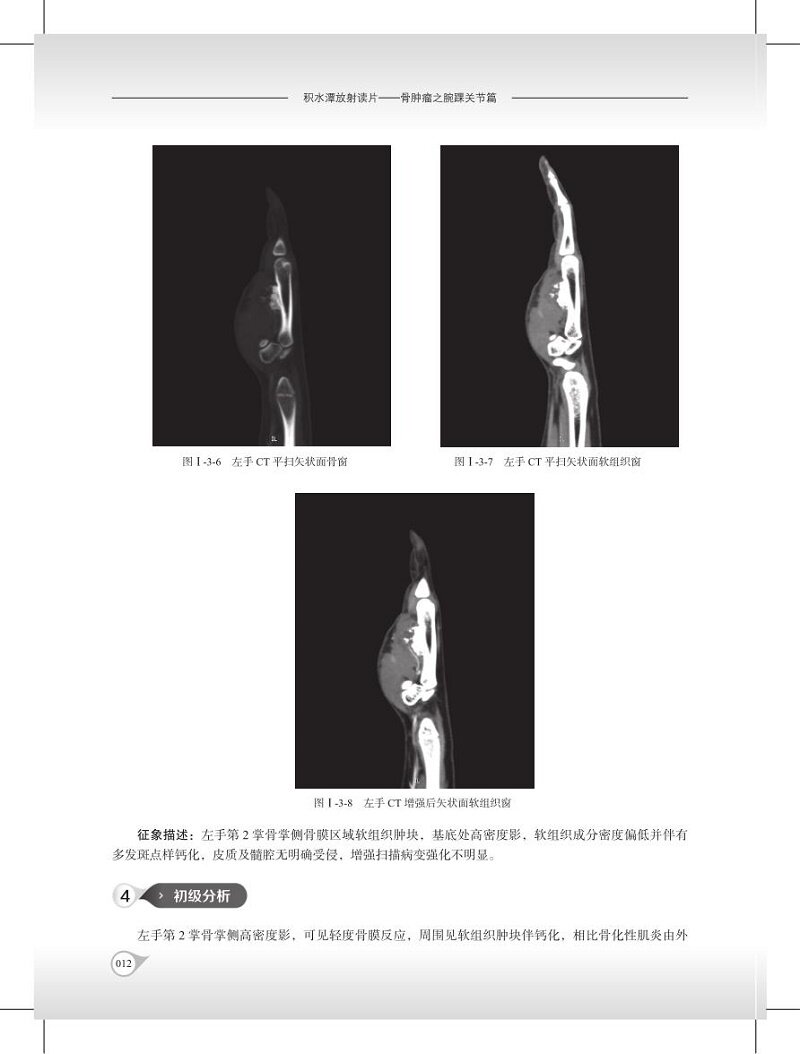

本书分部位选取病例,将X线检查、CT、MRI等多种影像学技术相结合,在病例分析中展示放射科的诊断思路、指出重要征象的价值。尽量保留了病例分析的实战特点。参与读片这均在不知病理结果的情况下进行影像分析,做出诊断。